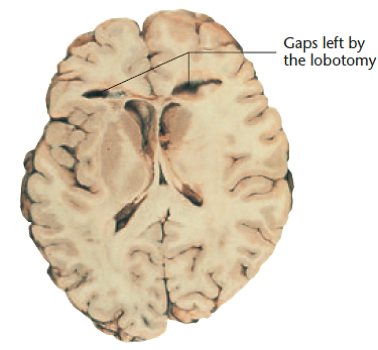

Lesion |

Ablation |

Removal of a brain area |